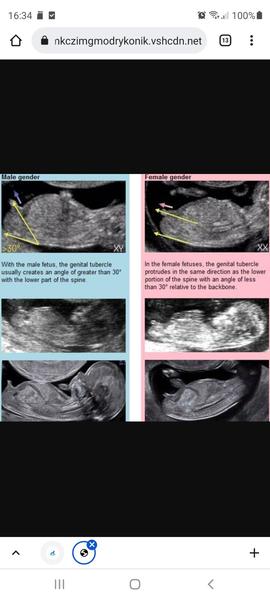

Pokud jsem správně pochopila, pokud je na ultrazvuku vidět výběžek, který směřuje nahoru, pak je to chlapec, pokud je ve vodorovném směru s tělem, pak je to pravděpodobně holčička.

@kaseenka pohlavní hrbolek je ten,co trčí nahoru,koukni se ke mě do alb,mám tam třeťátko,čtvrťátko a páťátko,tak se tam jukni na první screeningy a tam uvidíš rozdíl,u kluků ten pohlavní hrbolek šel nahoru,tak jak u tebe a u Anet šel ten pohlavní hrbolek vodorovně ♥

@vh1610 moc děkuji za krásnou fotku pro srovnání 🙂 já jsem se inspirivala na internetu dle přiložené fotky, ale nejsem tedy žádný odborník a ještě včera jsem netušila, že nějaký hrbolek vůbec existuje a je ukazatelem pohlaví, takže je to stále 50/50 a budu si muset počkat na odborný názor pana doktora 😄